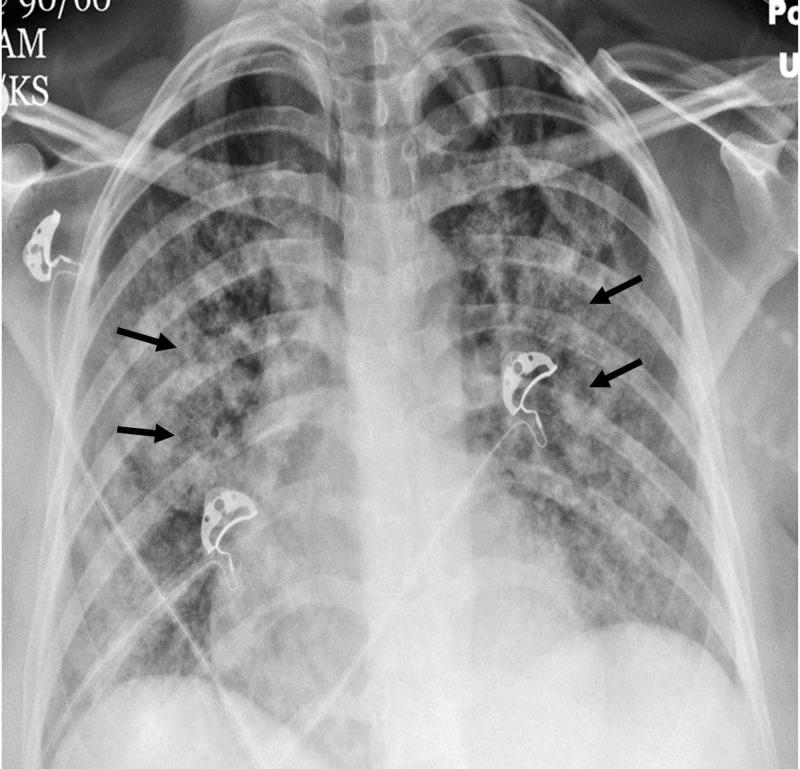

Acute chest syndrome (ACS), a vaso-occlusive crisis in patients with sickle cell anemia, is a life-threatening condition and a leading cause of death in these patients. It is treated with analgesics, antibiotics, intravenous fluid, supplemental oxygen (or ventilatory support in severe cases) with simple or exchange transfusion, being the mainstay of therapy. We report a young Jehovah's Witness (JW) patient with sickle cell anemia who presented with ACS. Her religious beliefs precluded the use of blood products. Despite concomitant hemolytic and aplastic crisis and a hemoglobin nadir of 3.1 g/dL, the patient was treated successfully with supportive care - including mechanical ventilation, sedation, paralysis, and erythropoiesis stimulation - and survived. A maximal supportive strategy consisting of ventilatory support with a high fraction of inspired oxygen, sedation, paralysis, erythropoiesis stimulation, and limitation of blood draws can result in the successful treatment of JW patients who refuse blood products.

急性胸部综合征(ACS)是镰状细胞贫血患者的一种血管闭塞性危象,是一种危及生命的病症,也是这些患者死亡的主要原因。其治疗方法包括使用镇痛药、抗生素、静脉输液、补充氧气(严重病例采用通气支持)以及简单或换血输血,这是主要的治疗手段。我们报告了一名患有镰状细胞贫血的年轻耶和华见证会(JW)患者,该患者出现了急性胸部综合征。她的宗教信仰使她不能使用血液制品。尽管同时出现了溶血性和再生障碍性危象,血红蛋白最低点为3.1g/dL,但该患者通过支持性治疗(包括机械通气、镇静、麻痹和促红细胞生成刺激)成功治愈并存活。由高浓度吸氧通气支持、镇静、麻痹、促红细胞生成刺激和限制抽血组成的最大支持策略可以成功治疗拒绝使用血液制品的JW患者。